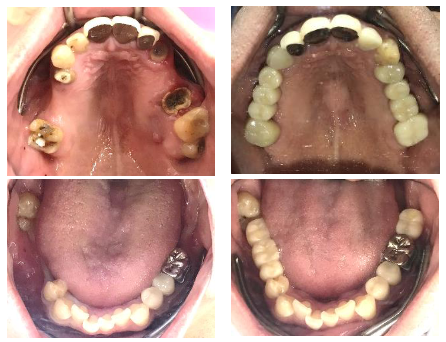

これまで他院で治療を受けられてきた40台前半の男性Yさんが、初めて当院に来院されました。

- 左上奥歯のブリッジが1ヵ月前にとれてしまった!

- 右上奥歯のブリッジが半年前にとれたが、そのままにしている!

- 右下の奥歯に部分入れ歯を入れたが、合わなくて使えなかった!

お口の中を精査したところ、顎の骨がしっかりしていて、残せそうな歯も多くありました。40代という若い年齢も考えて、「残っている歯に負担をかけないインプラント」をYさんにご提案しました。